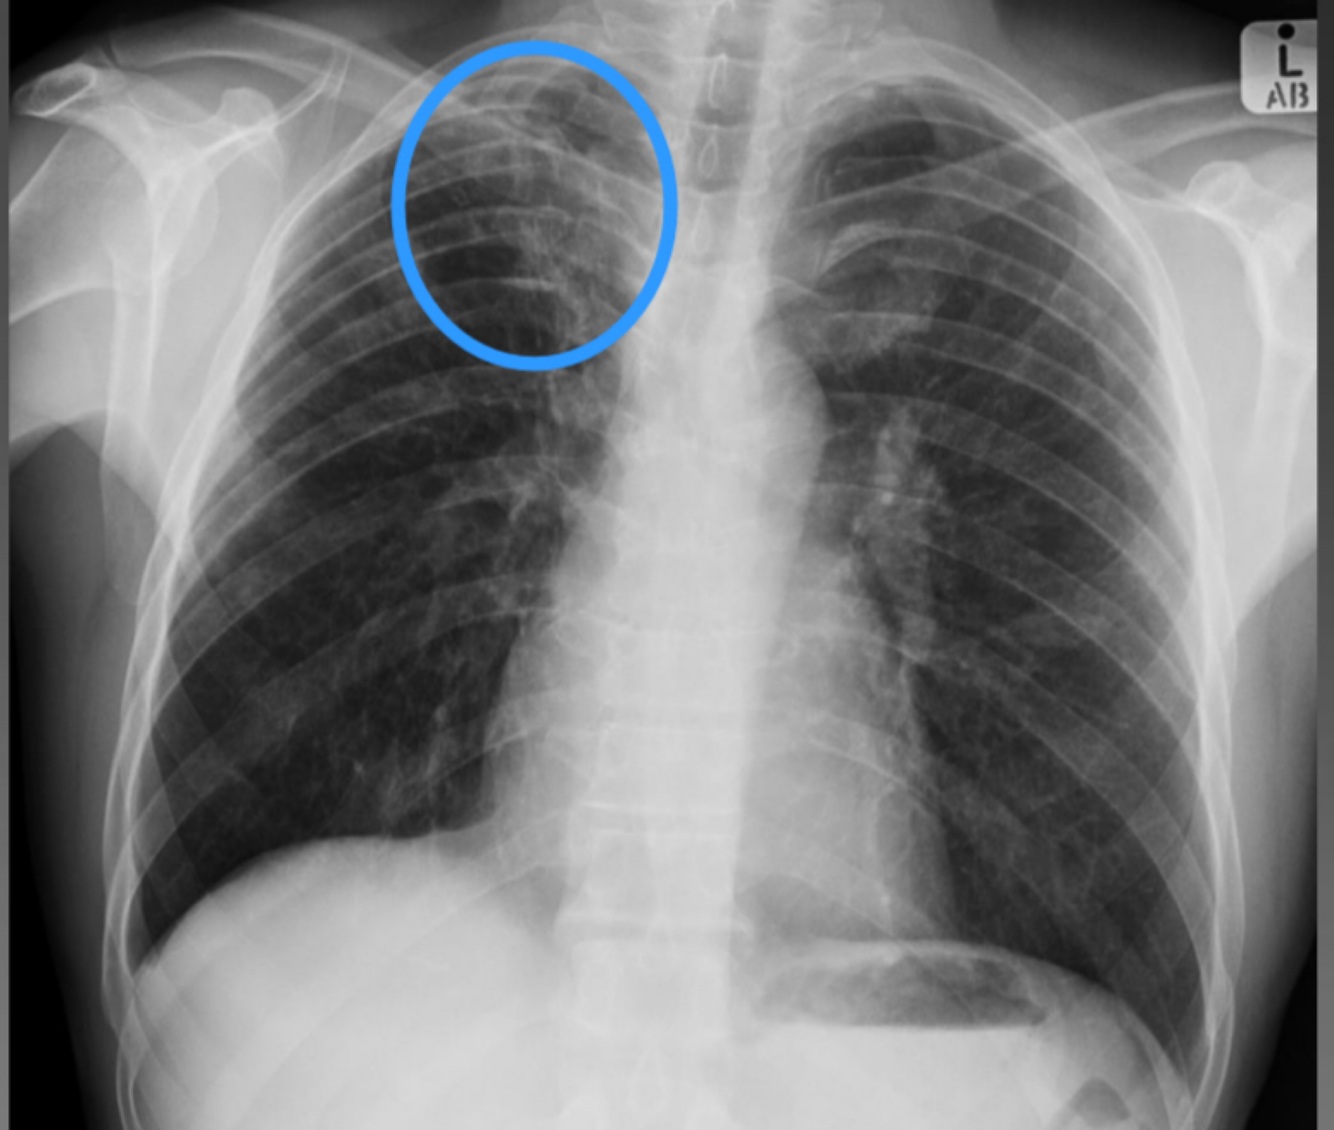

7

A

Consolidation and lymphadenopathy